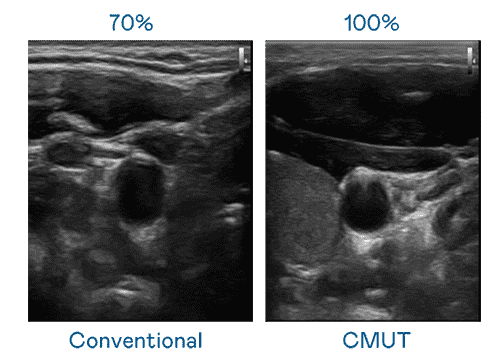

CMUT 技术是一种用电容式微机电元件来产生超音波讯号的技术。。。与传统 PZT 压电式技术相比,,,CMUT 频宽增加 30%,,,更宽频的超音波讯号让影像解析度大幅提升,,,是实现高影像品质医疗超音波扫描、、促进精准医疗发展的关键技术。。。。

大频宽带来超清晰影像

超音波影像的解析度高低,,首先取决于探头能发出的讯号频宽。。。。尊时凯龙 CMUT 可提供高清晰的超音波讯号,,,,提供高频宽、、高灵敏度、、、影像纹理细节更高的超音波影像,,,,协助医护人员缩短影像判读时间及利用精准的医疗影像进行诊断。。。